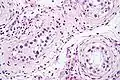

| Intratubular germ cell neoplasia. H&E stain. | |

GCNIS is not palpable, and not visible on macroscopic examination of testicular tissue. Microscopic examination of affected testicular tissue most commonly shows germ cells with enlarged hyperchromatic nuclei with prominent nucleoli and clear cytoplasm. These cells are typically arranged along the basement membrane of the tubule, and mitotic figures are frequently seen. The sertoli cells are pushed toward the lumen by the neoplastic germ cells, and spermatogenesis is almost always absent in the affected tubules. Pagetoid spread of GCNIS into the rete testis is common. Immunostaining with placental alkaline phosphatase (PLAP) highlights GCNIS cell membranes in 95 percent of cases. OCT3/4 is a sensitive and specific nuclear stain of GCNIS.[3]